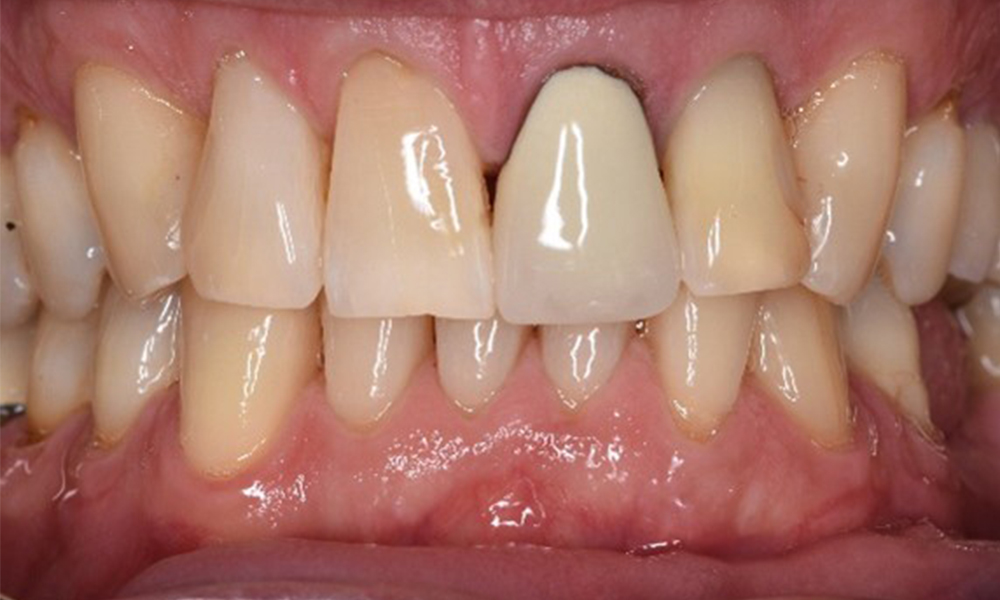

Case presentation: Complex Dental Prosthesis Management

The direct relationship between intraoral and general health, as well as the bidirectional influence that they may have on one another, is well-known (1,2). It is absolutely essential to consider both factors when planning preventive intraoral measures and treatment in the dental practice. The primary objective is the maintenance of patient health and quality of life from both dental and medical perspectives. more